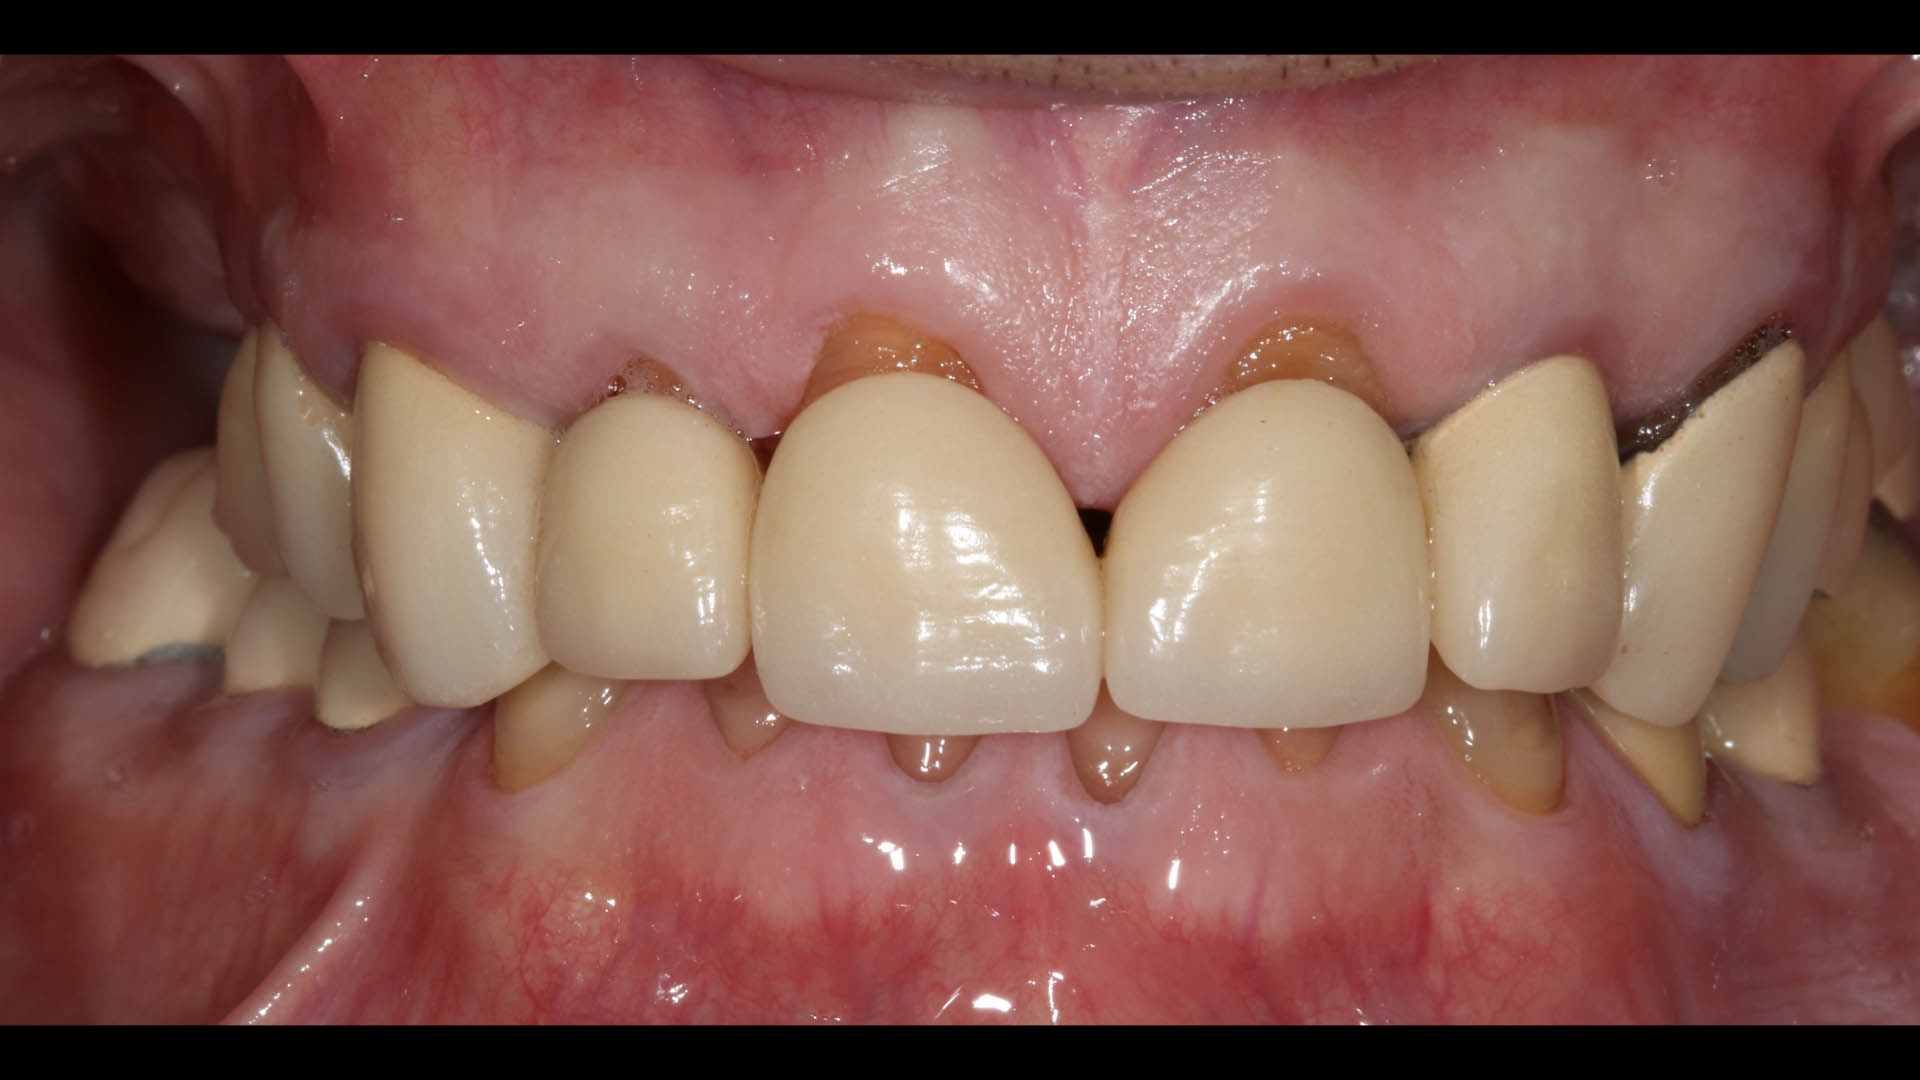

Take a glimpse into the magic of Coral Gables Dentistry through our before and after pictures. See firsthand the incredible smile makeover transformations that have brought confidence and joy to our patients.